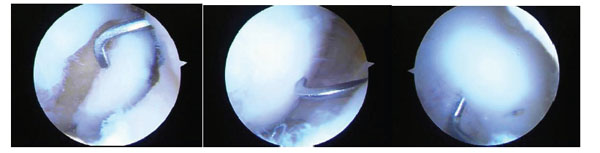

Fig. (8) A series of three arthroscopic images of a medial femoral condylar lesion due to osteochondritis dissecans. The cartilage is intact on the lateral side but the lesion can be mobilized on the cartilage hinge by the probe (left). After curetting of the fibrous tissue off the bone base and removing any dead bone, the lesion is reduced anatomically by the probe (central) and then fixed with bioabsorbable pins arthroscopically (right). One pin can be seen just to the right of the probe and the probe is used to check that the fixation is stable. Although this is a chronic lesion, the fixation principle is valid for acute lesions.